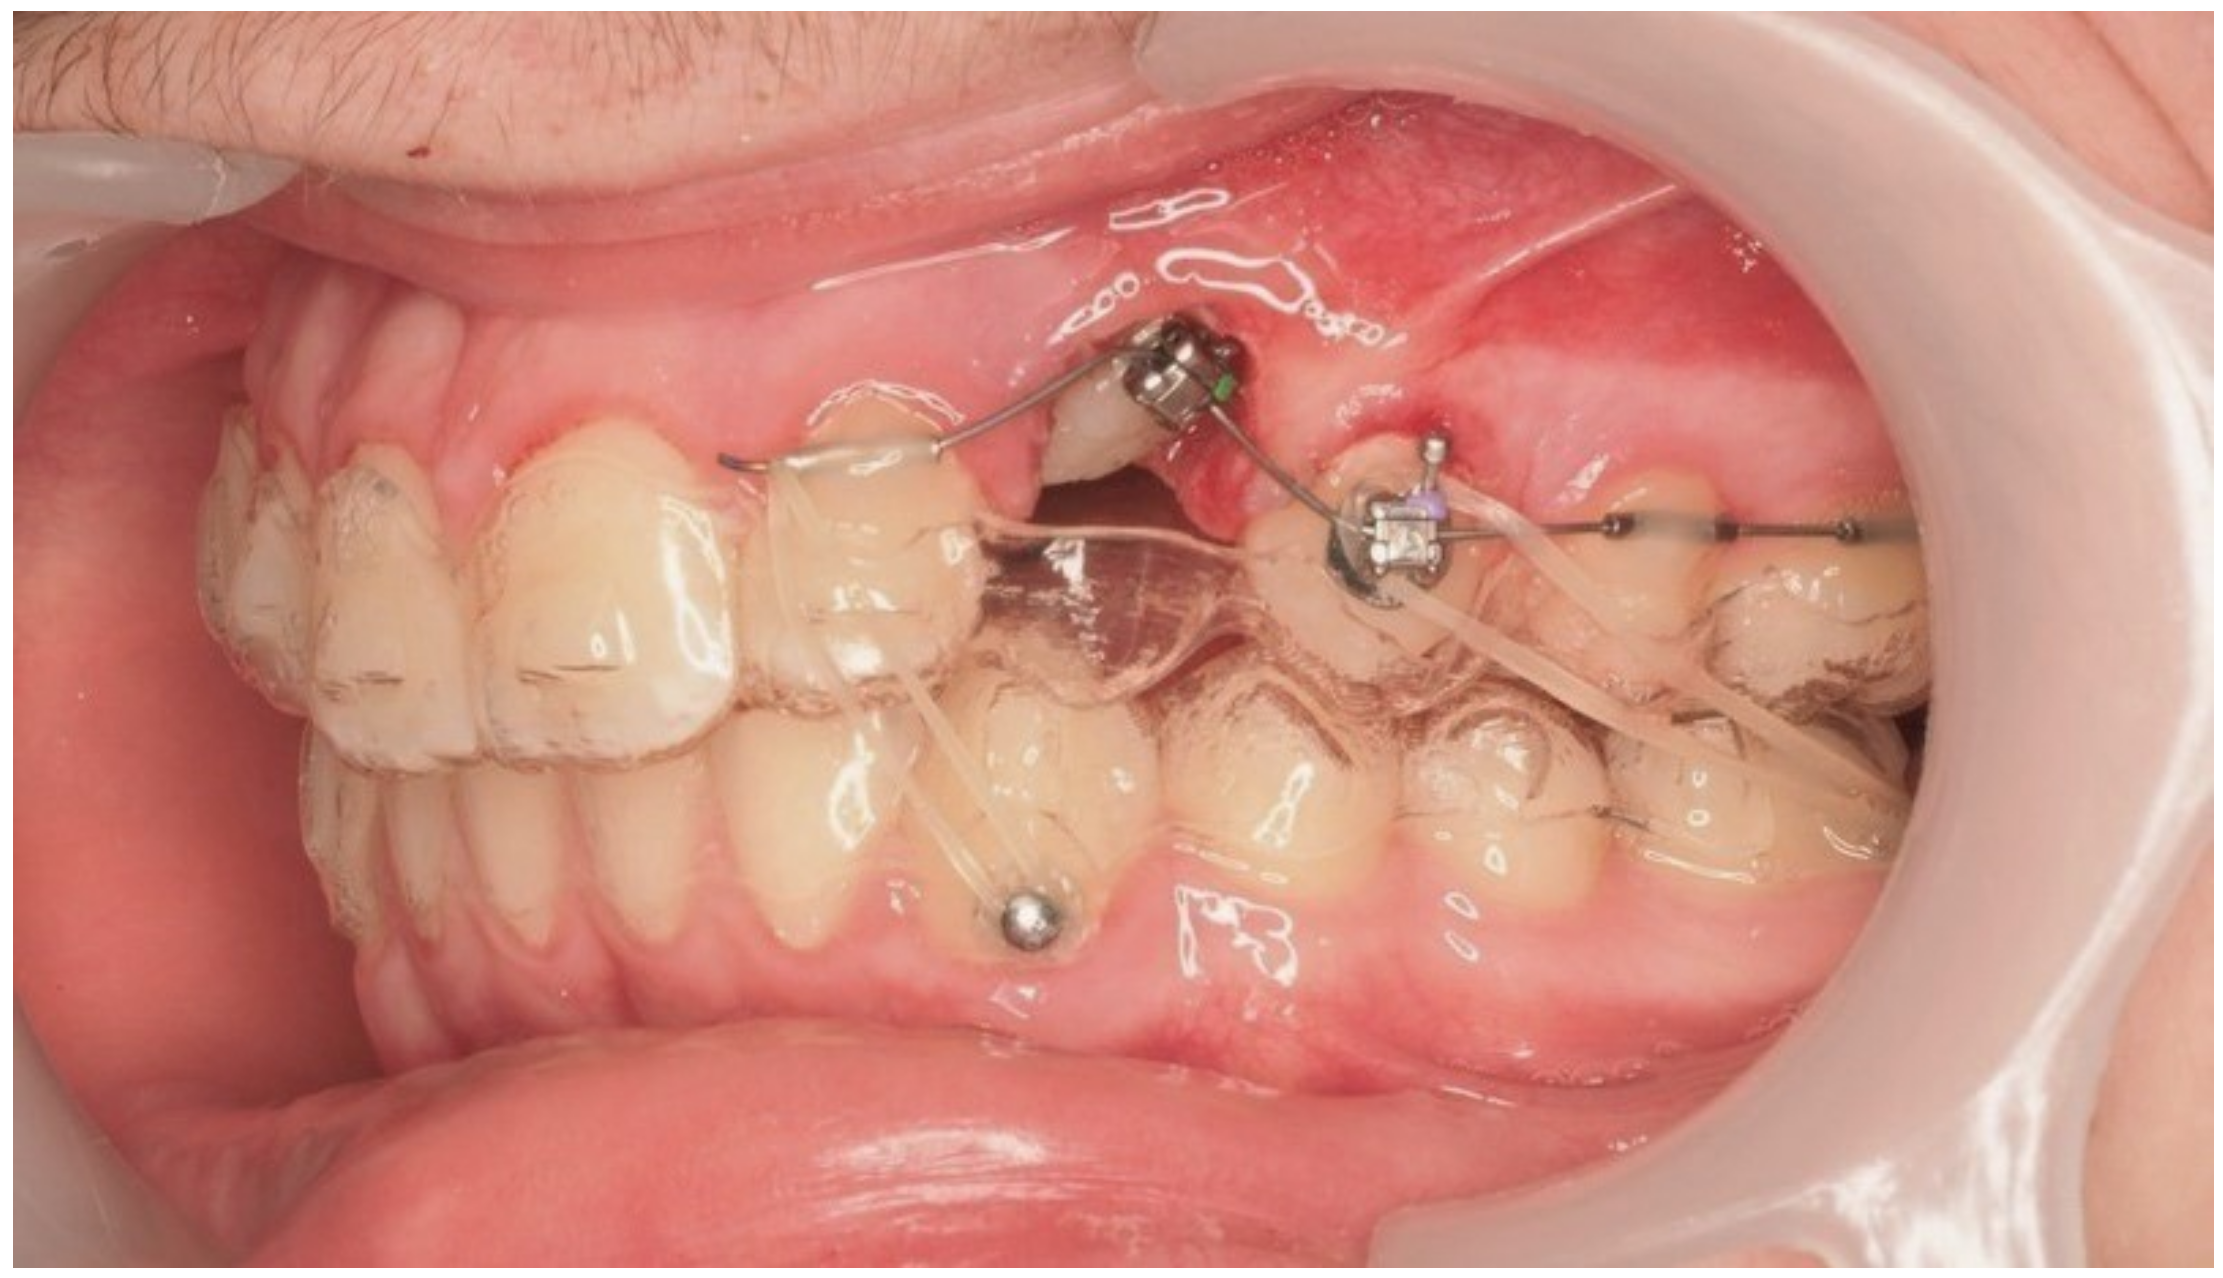

During vestibular traction, gingival removal was required. The canine presented mesial tipping and rotation. In the 14th month after the surgery, a bracket was bonded to tooth 23, following its inclination. A button was bonded on tooth 33 and connected by elastic to tooth 22 to stabilize the vertical position. Another elastic with a Class II vector was attached from the bracket on tooth 24 to a precision cut in the lower aligner (Figure 18).

Figure 18.

Vestibular traction of the canine, gingival removal, and elastic use for vertical stabilization; 14 months after the surgery.